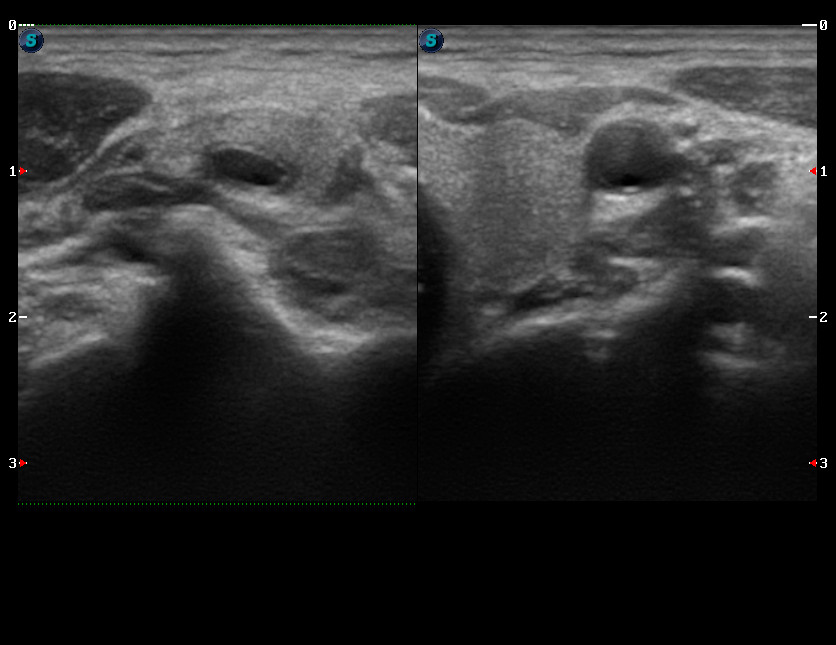

Молодая женщина, пришла с жалобами на болезненное образование на шее справа.

При сдавлении пораженная артерия очень легко компрессируется, в отличие от контрлатеральной.